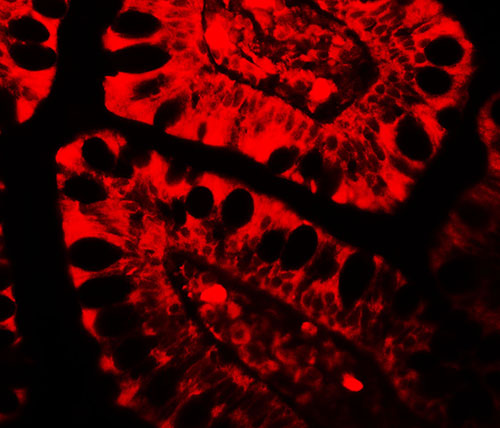

Immunofluorescence of TRIM21 in human small intestine tissue with TRIM21 antibody at 20 μg/mL. |